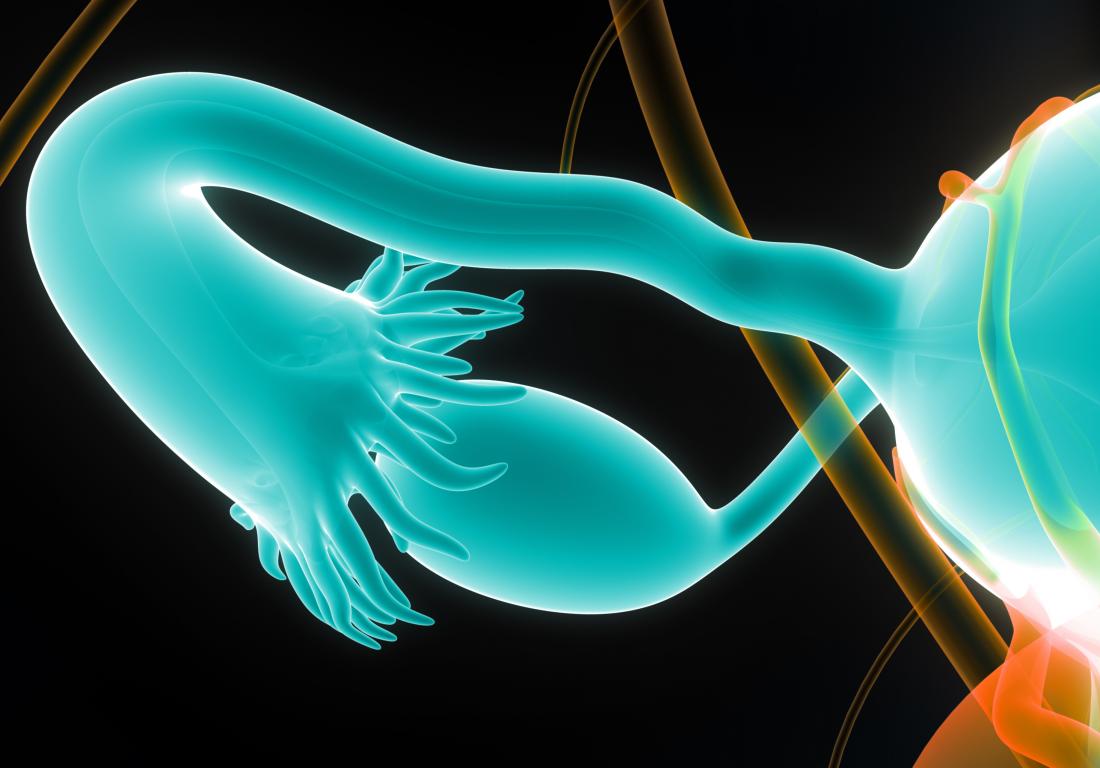

Fallopian Tubes Anatomy Function And Treatment 48 OFF

Real Fallopian Tube

Real Fallopian Tube